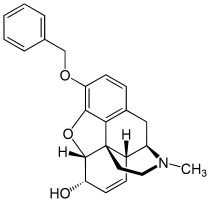

- Esters of morphine opiates: slightly chemically altered but more natural than the semi-synthetics, as most are morphine prodrugs, diacetylmorphine (morphine diacetate; heroin), nicomorphine (morphine dinicotinate), dipropanoylmorphine (morphine dipropionate), desomorphine, acetylpropionylmorphine, dibenzoylmorphine, diacetyldihydromorphine;[261][262]

- Semi-synthetic opioids: created from either the natural opiates or morphine esters, such as hydromorphone, hydrocodone, oxycodone, oxymorphone, ethylmorphine and buprenorphine;